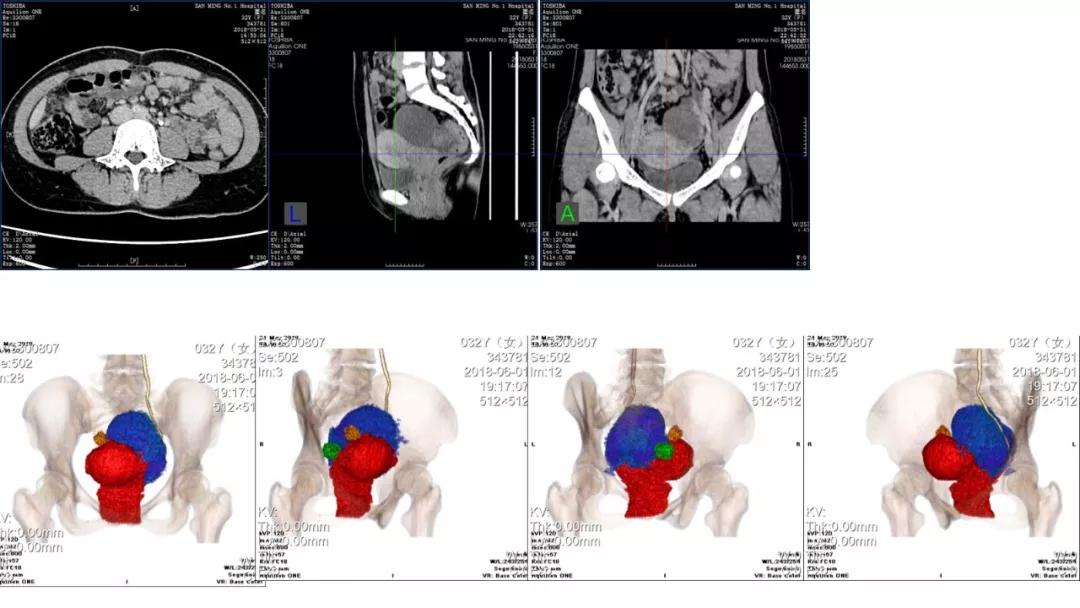

病例4 女,32岁,以“月经量增多伴经期延长半年。”

缘于患者入院前半年无明显诱因出现月经量增多,卫生巾由原来3包余增至5包不等,伴血块,经期由原来7天延长至10-15天不等,无痛经,无月经周期改变,无阴道异常排液,无畏冷、发热,无头晕、乏力等不适,未重视,未诊治。期间症状持续。2月前就诊我院,查彩超示:“子宫体大小约5.7*5.3*4.6cm,内膜厚约0.6cm,回声不均,左卵巢旁探及大小约4.2*3.5cm低回声区。”建议治疗,患者及家属表示考虑。期间症状持续,今就诊我科门诊,要求住院手术治疗,无腹痛等不适,门诊拟“卵巢囊肿”收住入院。既往史:2007年剖宫产一次,术顺。月经史:15 7/25 lmp2018.05.14,量中,无痛经。婚育史:已婚,1-0-3-1,末孕2007年剖宫产娩一男婴,儿子及丈夫体健。个人史、家族史均无特殊。

CA125 335.5(U/mL);2018-05-30 彩超:子宫宫体大小约5.6㎝×6.3㎝×4.9㎝,形态正常,宫壁回声欠均,内膜厚约1.8cm,回声不均。CDFI:子宫内未见明显异常彩色血流信号。左附件区探及一混合回声团块,大小约9.8㎝×7.9㎝,CDFI:其实性部分可见少许彩色血流信号。右附件区未见明显包块回声。

病理:卵巢子宫内膜样癌